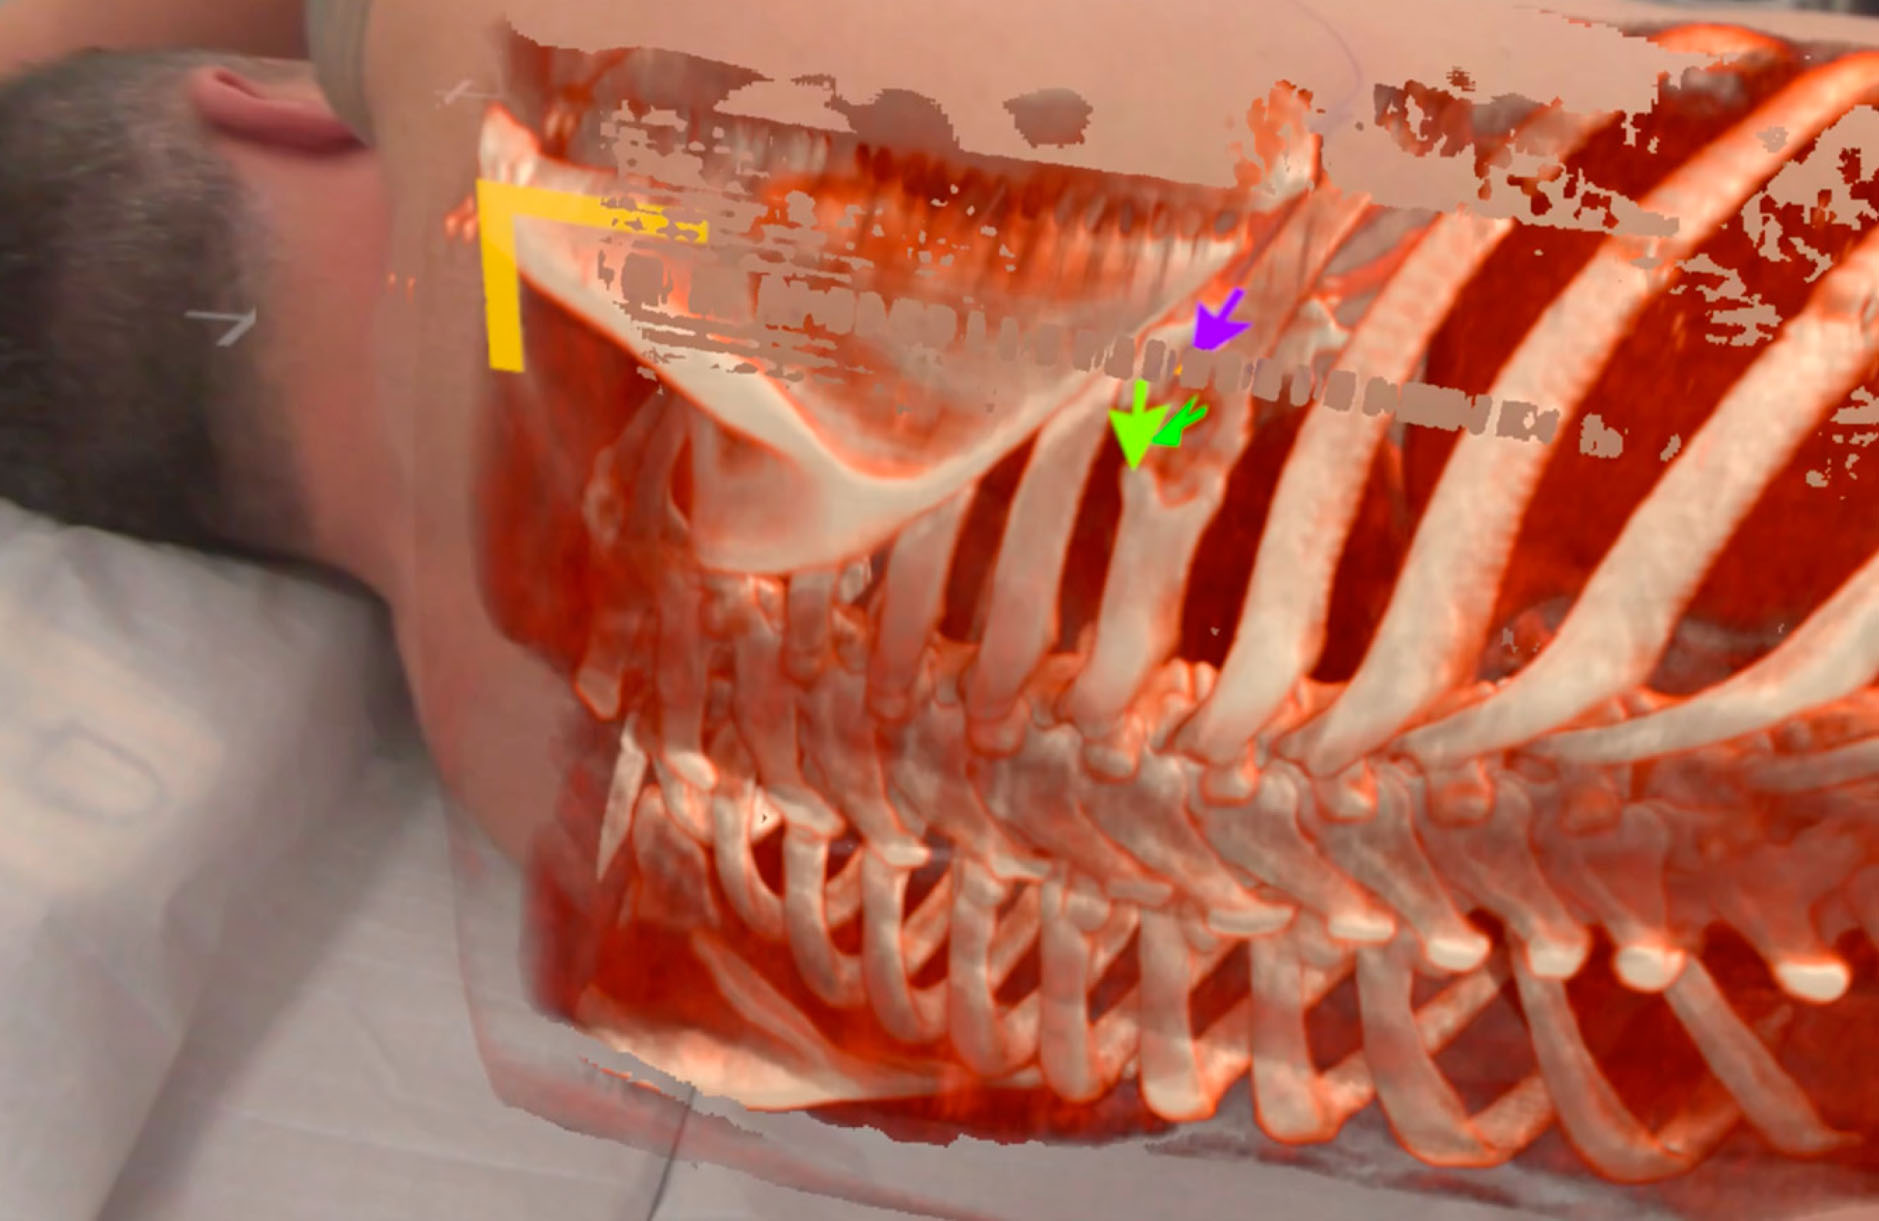

Transforming spinal surgery through medical VR.

How VR technology is transforming complex bone repairs in NHS Lanarkshire.

A leap forward in preoperative planning through holographic overlays and real-time 3D imaging.